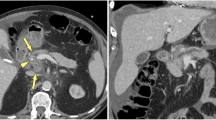

Significant differences in perfusion parameters were noted between tumors and normal parenchyma in PDAC cases (p < 0.001), as shown in Table 1 (Fig. 3A–C). Perfusion values for tumors in PDAC cases were found to be lower than those for normal parenchyma by 84.2%–85.2% for BV, 73.5%–75.1% for BF, and 75.8%–78.0% for PS, while MTT was 67.4%–68.7% longer (readers 1 and 2, respectively).

A 65-year-old female patient whose PDAC was pathologically confirmed. (A) Hypoattenuating tumor located in pancreatic tail is seen on CECT (arrow). (B, C) On BV, BF, MTT, and PS maps, lesions (arrows, circle) with lower perfusion and prolonged transit times compared to normal parenchyma (circle) can be monitored visually and by the results of the measurements

Significant differences in perfusion parameters were noted between lesions and normal parenchyma in MFCP cases (p < 0.05), as shown in Table 2 (Fig. 4A–C). Perfusion values for lesions in MFCP cases were found to be lower than those for normal parenchyma by 41.9%–44.6% for BV, 38.7%–38.6% for BF, and 33.4%–31.7% for PS, while MTT was 45.8%–42.9% longer (readers 1 and 2, respectively).

A 51-year-old male patient whose MFCP was pathologically confirmed. In the case, malignancy did not develop during the 18-month follow-up period. (A) An isoattenuating mass view with parenchyma in the body of pancreas is monitored on CECT (arrow). (B, C) On BV, BF, MTT, and PS maps, lesions (arrows, circle) demonstrated low perfusion and prolonged transit times compared to normal parenchyma (circle) can be monitored both visually and by the results of the measurements